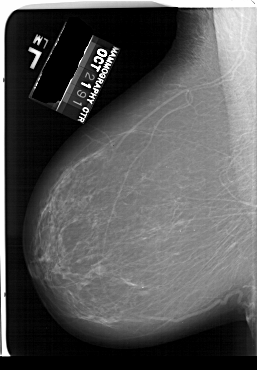

A_1632_1.LEFT_MLO

LEFT_MLO LINES 6646 PIXELS_PER_LINE 4621 BITS_PER_PIXEL 12 RESOLUTION 43.5 NON_OVERLAY